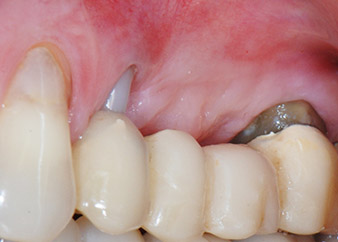

Résultat intermédiaire à deux mois

Les figures 17 et 18 présentent le résultat clinique deux mois après l'intervention chirurgicale. La dent 24 présentait une mobilité réduite, de classe I (Miller) et les tissus mous ne présentaient aucune inflammation. Pour prévenir toute nouvelle infection et pour éviter d'endommager l'attache épithéliale, aucun test n'a été pratiqué à ce stade. Une visite de contrôle a été programmée pour la prochaine incision et la mise en place des parties secondaires de cicatrisation, six mois après l'insertion des implants.

Deux mois après l'intervention chirurgicale

Fig. 17 : Deux mois après l'intervention chirurgicale, la patiente ne ressentait plus aucune douleur et la région ne présentait plus d'inflammation.

après le chirurgie

Fig. 18 : La dent 24 présentait alors une mobilité réduite.

À la consultation des deux mois, la mobilité de l'« élément dentaire » 24 restant était déjà passée de Miller 2 à Miller 1. L'attache des tissus mous était au niveau de la dent voisine 23. De plus, en l'absence de symptômes endodontaux ou parodontaux, son pronostic devra peut-être être révisé.